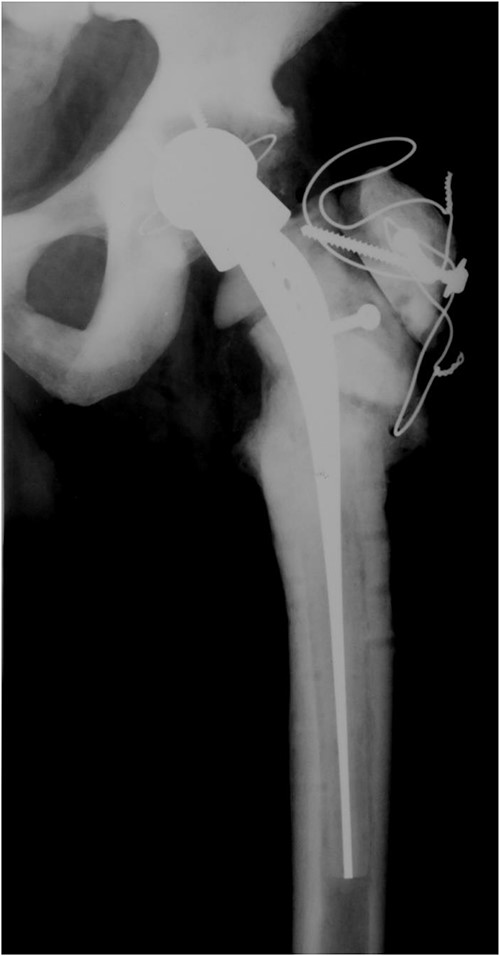

In 2011, a cementless THA of the right hip was done for the osteoarthritis. Three residual broken screws were present in the distal diaphysis from previous surgeries and were left in place (Fig. 3).

Anteroposterior radiograph of the right hip after THA with three broken residual screws in the distal diaphysis. (a) Anteroposterior hip radiograph with broken lateral plate. (b) Anteroposterior radiograph of the right hip after exchanging the femoral stem.

In 2013, the patient suffered a spontaneous Vancouver B2 periprosthetic fracture of the right THA. Osteosynthesis with a locking plate with screws and cerclages was done. Three months after the surgery, the plate broke and was exchanged with addition of an anterior plate and autologous spongioplasty. However, osteosynthesis failed 8 months later and the firmly ingrown femoral component was revised (Fig. 3a). Proximal femoral osteotomy resulted in several broken fragments. During removal of the broken screws, three sets of removal instruments were destroyed. A cementless revision modular stem was inserted and bone fragments fixed with cerclage wires and titanium tapes (Fig. 3b). Surgery took 6 h and he received six units of blood. Microbiological tissue samples were negative.